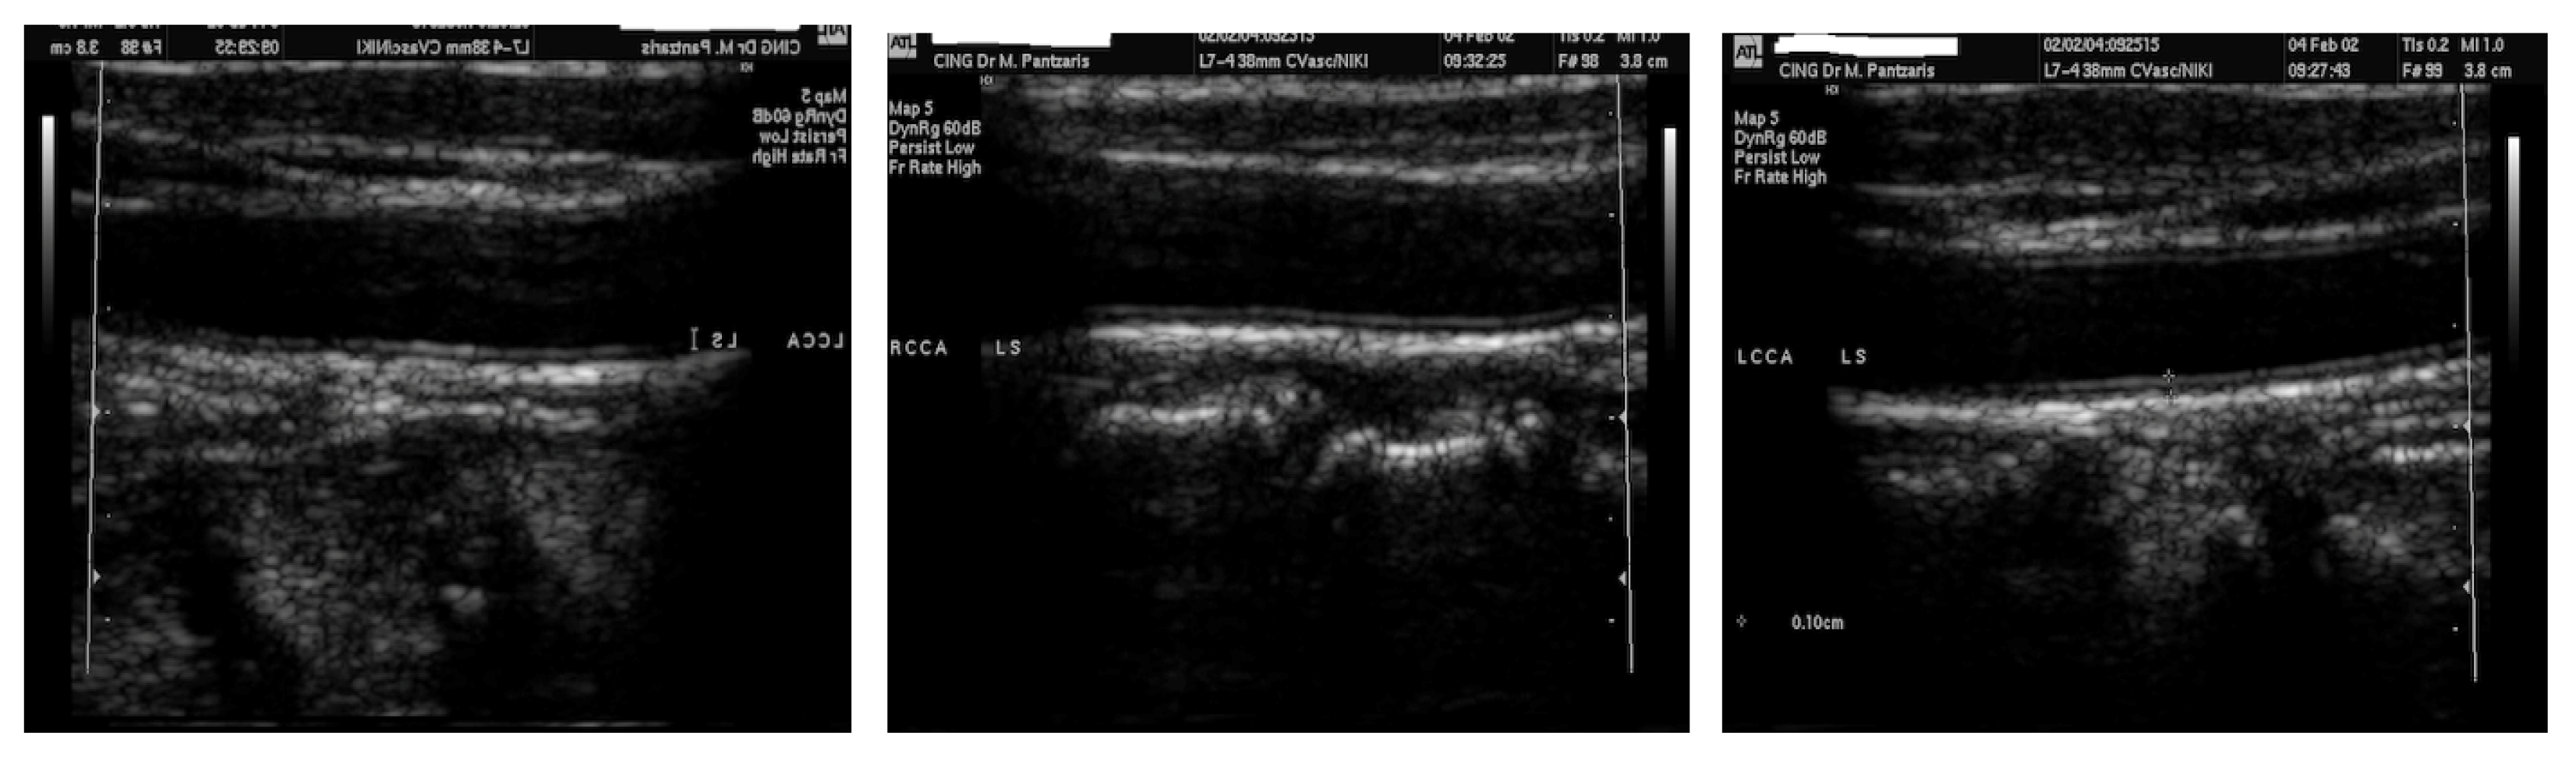

The dataset used for this paper is a dataset in [8]. It contains 100 carotid IMT B-Mode ultrasound images with their ground truth points determined by two clinical experts. In their work, Loizou et al. [8] highlighted that images were taken from 42 female and 58 male symptomatic patients aged between 26 and 95, where they produced longitudinal ultrasound images.

The images were obtained from the ATL HDI–3000 scanner (Advanced Technology Laboratories, Seattle, WA, USA), and were logarithmically compressed to produce images with 768 × 576 pixels resolution and 256 grey levels. The scanner has a multi-element ultrasound scan head with an operating frequency range of 4–7 MHz, an acoustic aperture of 10 × 8 mm, and a transmission focal range of 0.8–11 cm, with 64 elements fine pitch high-resolution, and 38 mm broadband array. Furthermore, the bicubic method was used to resize digital images to a standard pixel density of 16.66 pixels/mm.

Figure 2 illustrates three sample images from the dataset that we work within this paper. Given that the ultrasound image is all that is required, the frames in the samples that included patient information were removed as part of the pre-processing step.